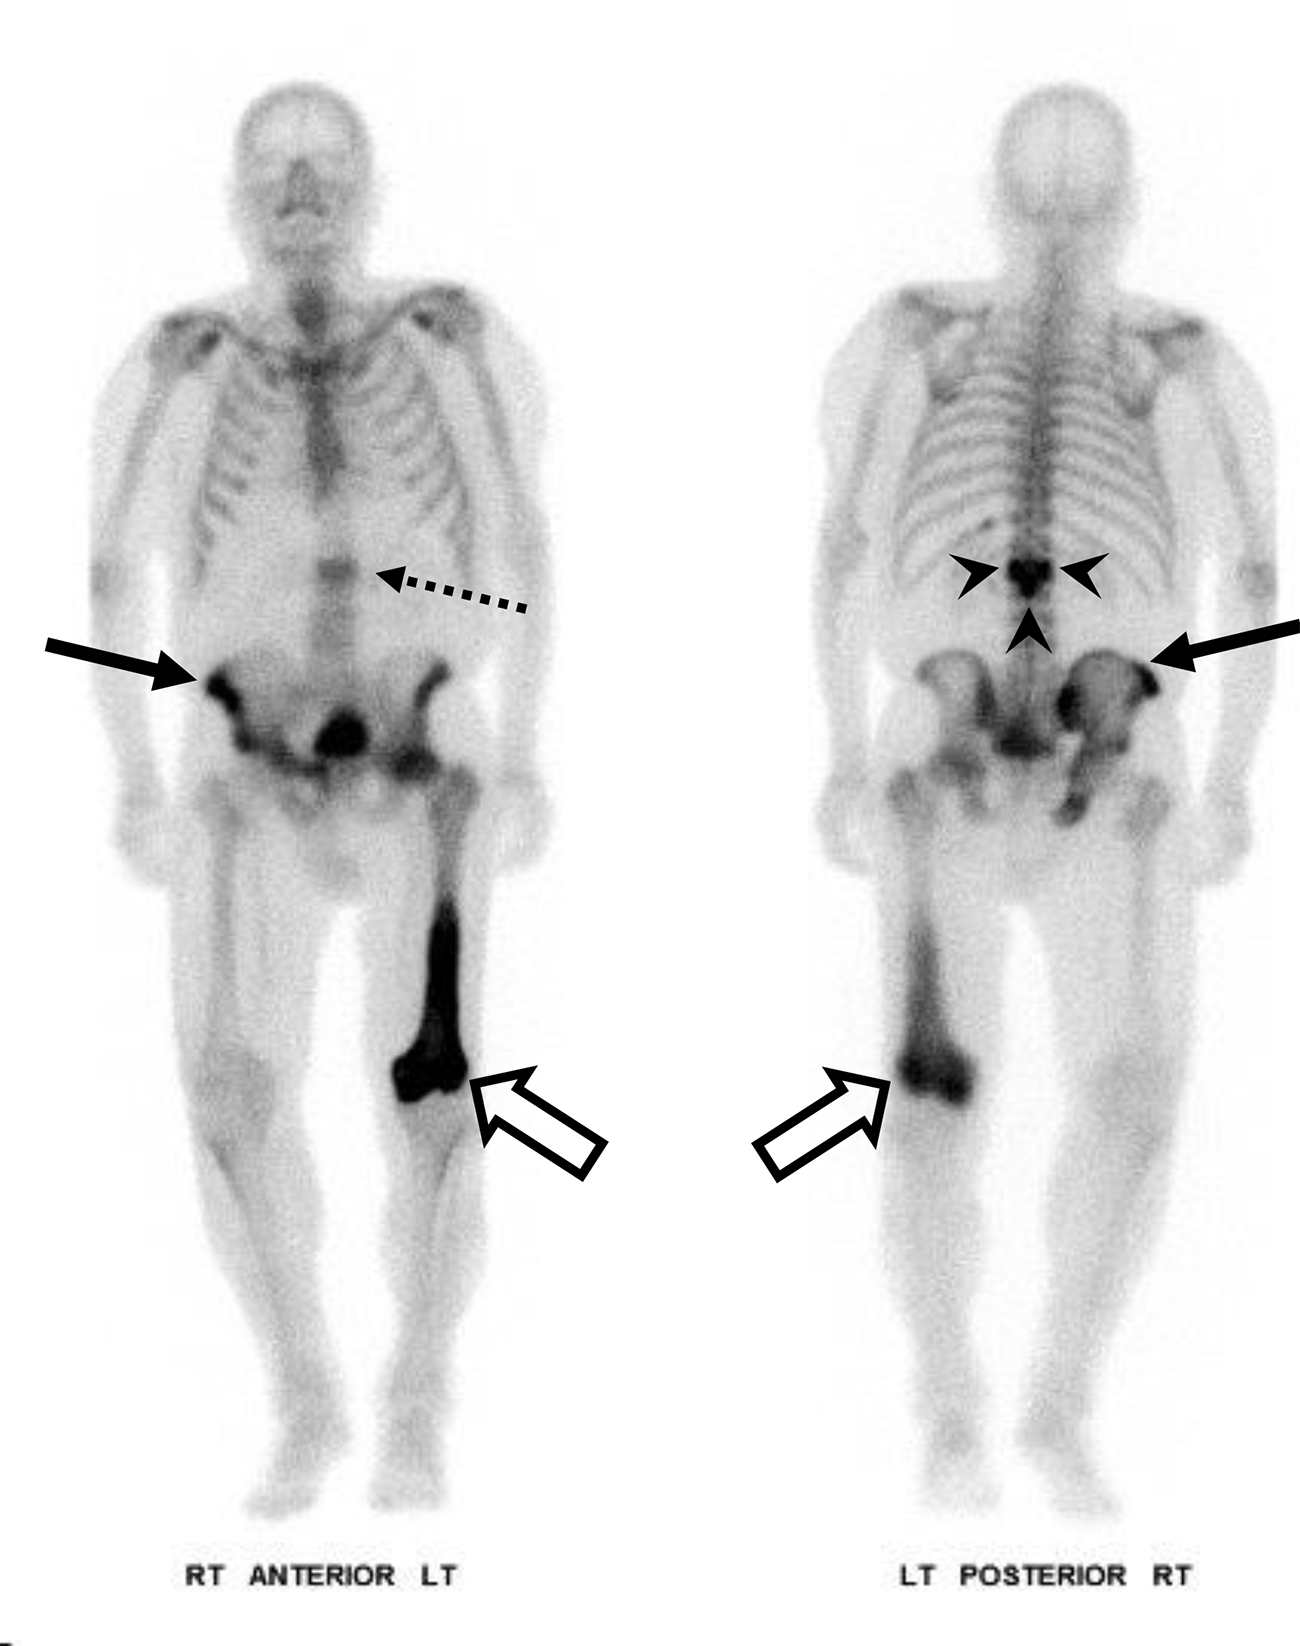

Osteoartropatia Ipertrofica (HOA) in un uomo di 56 anni con noto tumore al polmone.

L’indagine scintigrafica evidenzia una caratteristica ipercaptazione lineare corticale lungo le diafisi delle ossa lunghe tubolari (e bilateralmente a livello zigomatico). Questo pattern simmetrico e periferico è noto come segno del “binario del tram” (tram-track sign).

L’imaging tradizionale conferma la base fisiopatologica del reperto scintigrafico, mostrando una reazione periostale (apposizione di nuovo osso lamellare) a livello metadiafisario.

L’osteoartropatia ipertrofica (che in questo caso rappresenta una sindrome paraneoplastica, spesso secondaria a tumori polmonari) è caratterizzata da una classica triade clinico-radiologica: periostite diffusa delle ossa lunghe, ippocratismo digitale (dita a bacchetta di tamburo) e manifestazioni artritiche/artralgiche. La scintigrafia ossea è estremamente sensibile nell’identificare l’attività periostale in fase precoce.